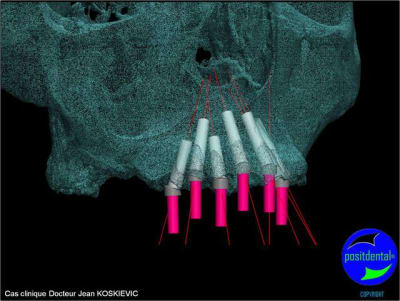

et la projet 10 implants maxillaire sup

10 en haut